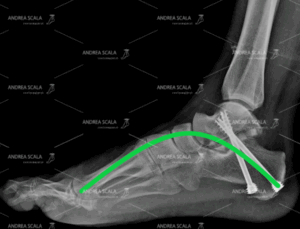

La RXgrafia post-operatoria mostra che l’arco del piede è stato ricostruito. L’articolazione ammalata ha dovuto essere asportata perché causava un grande dolore. Per rifare l’arco sono state necessarie due viti metalliche che tengono insieme il montaggio.